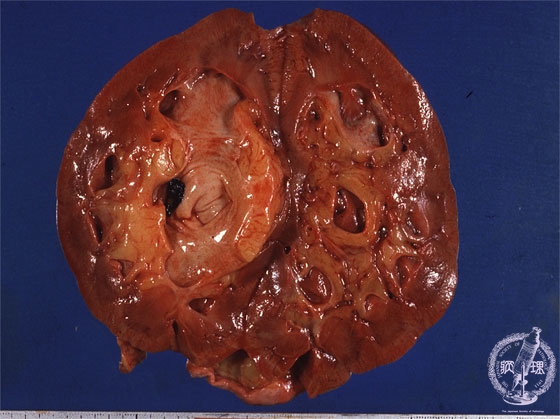

- (14)Nephrolithiasis

Gross findings: The renal pelvis contains a black-colored concretion (yellow arrow). This case also presents hydronephrosis. Note the dilated pelvis (yellow dotted line).